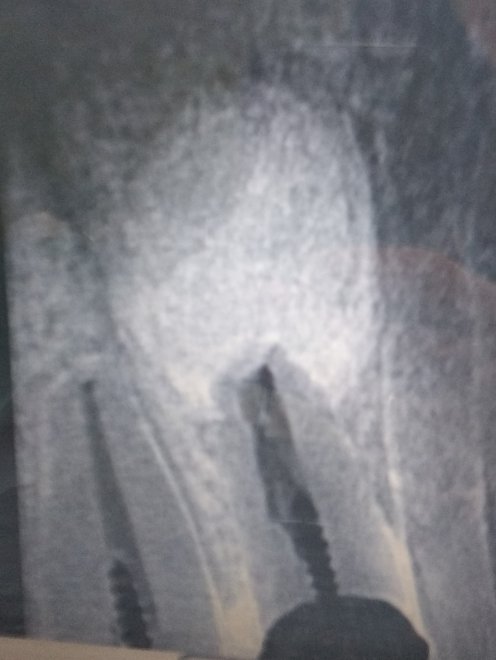

ще один знімок